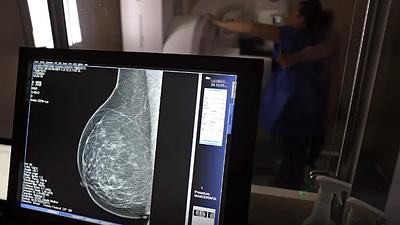

Pesquisa em larga escala aplica IA para detectar câncer de mama

A ferramenta de IA foi aplicada em tempo real e envolvendo um grupo ampliado de pessoas, em vez de ser utilizada posteriormente como vinha sendo feito até agora.

Super Centro usa IA em diagnósticos de câncer de mama

Os laudos dos exames de mamografia realizados no Centro Carioca de Diagnóstico e Tratamento por Imagem (CCDTI) são avaliados e assinados por profissionais médicos capacitados, no entanto, a IA auxilia na identificação de possíveis lesões difíceis de serem vistas.